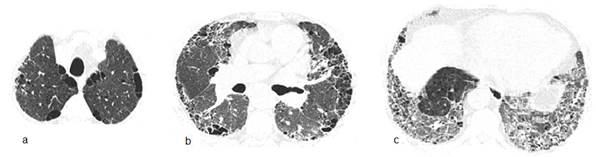

Varón de 66 años, fumador de 90 cajas/año. Taxista. Artritis reumatoide de 5 años de evolución con uso irregular de prednisona y leflunomida. Consultas previas en varios hospitales. Disnea hace 1 año progresiva hasta mínimos esfuerzos y dos episodios de sincope. Dolores de mano y rigidez matutina de articulaciones metacarpo falángicas ocasionales. Niega fiebre. Frecuencia respiratoria 20xmin, frecuencia cardiaca 98xmin; SatO2 90%; Crepitantes finos bilaterales bibasales. Leucocitos, 10800/mm3; VSG 24 mm, PCR (-), FR (++), Anti CCP (++), HIV (-). La TACAR de tórax se muestra en la figura 1. Espirometría: capacidad vital forzada (CVF) 59% del valor previsto, volumen espiratorio forzado en el primer segundo (VEF1) 67% del previsto y VEF1/CVF 78; Test de marcha de 6 minutos (TM6M): 65% recorrido de distancia prevista con SatO26%; Ecocardiografía informa presión sistólica de arteria pulmonar (PSAP) 45mmHg: Gasometría arterial: pH 7,43 PaO2 57 torr PaCO2 29 torr SatO2 90%. Se niega a internación. Se sugiere oxigenoterapia, inmunizaciones pertinentes, tratamiento para cese de tabaquismo y de enfermedad pulmonar intersticial e interconsulta con reumatología. El diagnóstico inicial es de síndrome de combinación de fibrosis pulmonar y enfisema más hipertensión pulmonar, asociados a artritis reumatoide.

El síndrome combinado de fibrosis pulmonar y enfisema (SCFPE) generalmente se observa en hombres con alta carga de tabaquismo que refieren disnea progresiva y presentan crepitantes posterobasales a la auscultación torácica. La TACAR es el pilar diagnóstico ya que muestra el componente enfisematoso (paraseptal, centrilobular o panlobular) en la región superior y el componente intersticial (neumonía intersticial usual, neumonía intersticial no específica o neumonía intersticial descamativa) en la región inferior12. Las mediciones en espirometría no son tan características como la disminución en la DLCO y en las variables obtenidas en el TM6M13. En el caso aquí reportado podemos constatar estas características funcionales que también podrían ser expresión vectorial de la hipertensión pulmonar, entidad invocada como desenlace relevante del SCFPE14. Sin embargo, lo más resaltante es la asociación del síndrome con la artritis reumatoide (AR) en la cual debe considerarse como una manifestación diferenciada en el espectro del “pulmón reumatoide” en fumadores o ex fumadores. Generalmente y comparada al SCFPE idiopático, se da en individuos más jóvenes, puede anteceder al cuadro florido de la AR y conlleva mejor pronóstico15. Se describe que la esclerosis sistémica, la enfermedad mixta del tejido conectivo, la poliangitis microscópica, la asbestosis y la silicosis también pueden estar asociadas12.

La neumonitis intersticial descamativa, diagnostico probable del segundo caso, es una enfermedad poco frecuente que se adscribía exclusivamente al hábito de fumar, sin embargo una revisión reciente encontró que hasta el 19% puede asociarse a otras causas16. La disnea y la tos (de 13 meses de evolución en promedio) en el contexto de un patrón funcional restrictivo junto a opacidades en vidrio esmerilado en regiones inferiores a la TACAR torácica, constituyen el escenario clínico usual. La confirmación histopatológica no se realizó debido al alto riesgo que suponían los procedimientos invasivos en el paciente. Nótese que en la figura 2 hay concomitancia de enfisema paraseptal y AEAF, lo que evoca ciertas formas de SCFPE. La DIP no es tan benigna como imaginamos, ya que conlleva 25% de mortalidad con variable y heterogénea respuesta (65%) al tratamiento (cese de tabaco y corticoides) pudiendo mostrar recidiva hasta en 18% después de completar la terapia17.